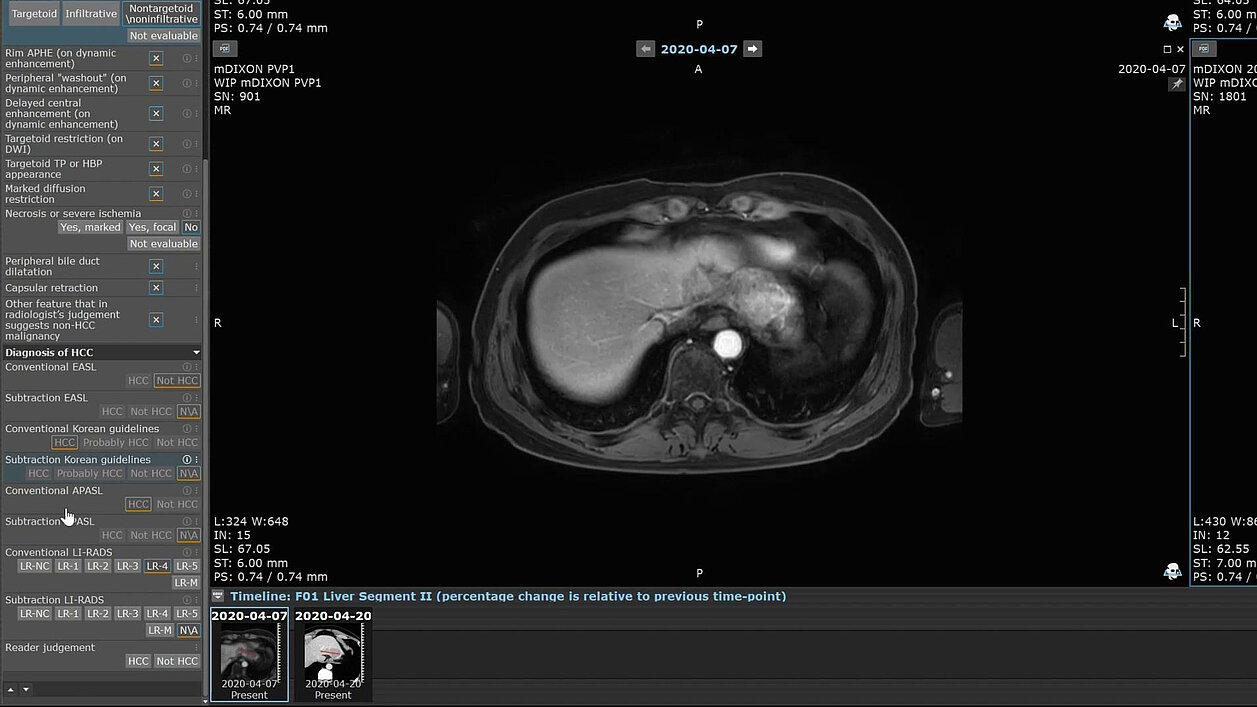

Zwei der Autor:innen arbeiteten mit dem Entwicklungsteam von Mint Medical zusammen, um eine mint Lesion™-Vorlage zu erstellen, die häufige Bildgebungsmerkmale und präzise automatische diagnostische Zuordnungen aus den vier Leitlinien (AASLD/LI-RADS, KLCA-NCC, EASL und APASL) integriert.

„Diese Zusammenarbeit zielte darauf ab, einen nahtlosen automatischen Diagnoseprozess zu implementieren, auf dessen Grundlage ein elektronischer Fallbericht generiert wird“, erklärten sie. „Insgesamt wurden 46 Fragebögen für jede FLL bereitgestellt, die Hauptmerkmale, Targetoid- und Non-Targetoid-LR-M-Merkmale, das Vorhandensein von Tumorgewebe in einer Vene (LR-TIV-Kategorie) und zusätzliche Merkmale behandelten.“